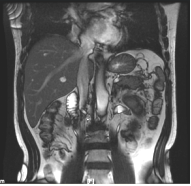

(2022.9.11)MR: 1.降结肠癌肝转移化疗后复查,较前片病灶稍缩小,请结合临床2.右肝后叶上段转移瘤,较前明显缩小,余未见显示3.左肾占位,错构瘤可能,较前相仿4.双肾多发囊肿。

image.pngimage.png